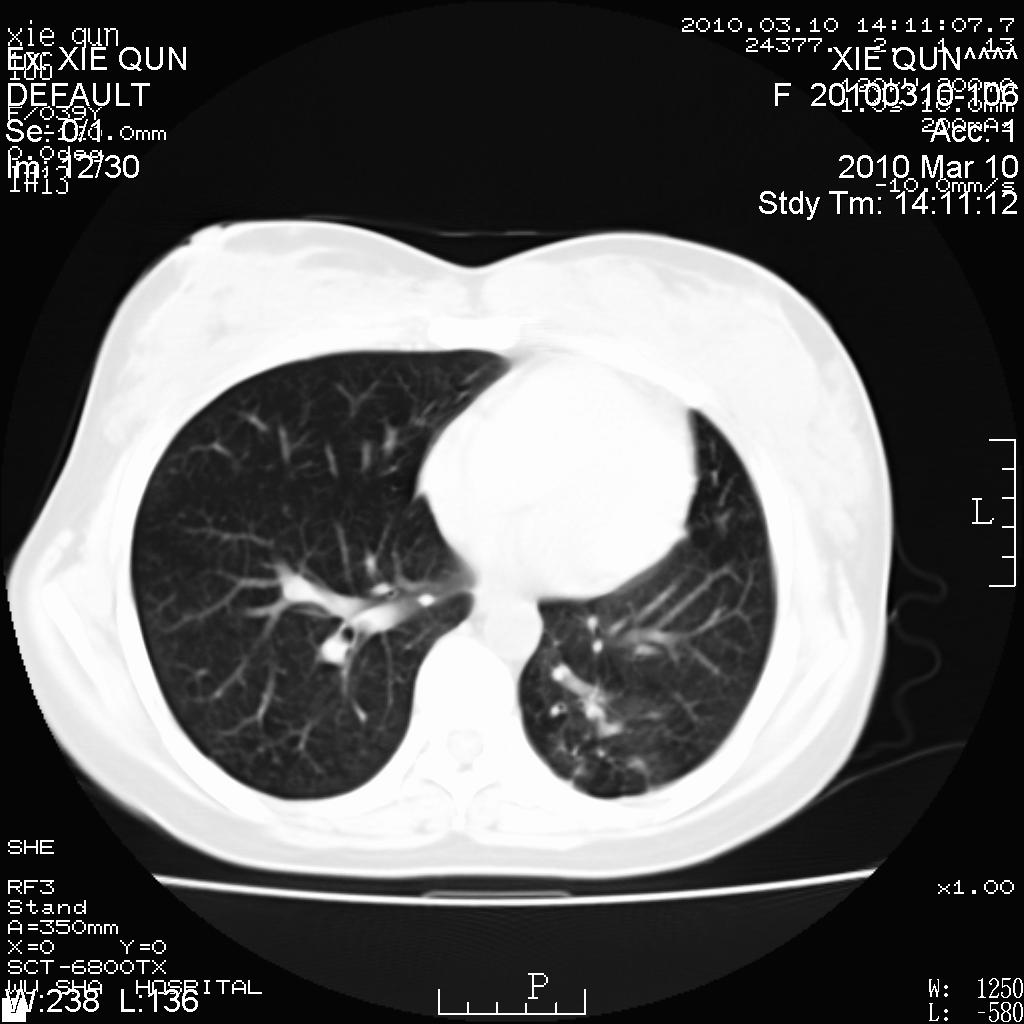

以下是引用心路寻觅在2010-3-24 17:28:00的发言:[br]两肺继发性tb左上肺空洞形成,建议痰检明确诊断。

以下是引用随光逐影在2010-3-24 19:19:00的发言:[br]两肺继发性结核并左上肺上叶空洞形成。